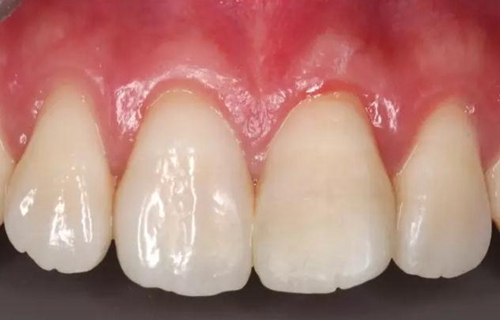

患者1個(gè)半月后復(fù)診,口腔衛(wèi)生狀況保持良好,牙齦健康,折斷線不可見(jiàn)。